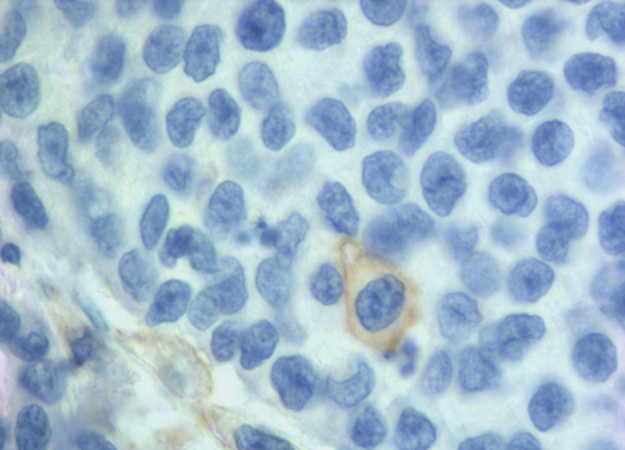

PD-L1 staining was observed with different rate both in neoplastic cells (NCs) and in infiltrating immune cells (IICs). NCs were positive in 25% of samples, while IICs in 78% (Table 2). The normal colonic mucosa did not show any staining. A predominately membranous staining was observed in positive NCs cells. In these cells either a focal or a diffuse PD-L1 positive pattern, with the prevalence of the former was detected. When the pattern was focal, the positivity of NCs was prevalently localized along the tumor-stromal interface. Rarely scattered single or small nests of positive NCs dispersed in an otherwise negative tumor plate were observed. In IICs the membranous expression was more difficult to distinguish and a diffuse positive pattern was prevalent. Representative images of PD-L1 expression in NCs and IICs are shown in Figure 1.

Figure 1: IHC expression of PD-L1 in NCs and IICs. (A and B) representative diffuse and focal expression in NCs; (C and D) representative diffuse and focal expression in IICs.

We found 25% of cases with PD-L1 positive in NCs and 78% in IICs. Our positivity rate is higher than that described in other studies using the same MAb E1L3N and the same 5% cut-off [11, 39, 42, 43]. Our results can be due to several factors. We carried out the immunohistochemical detection on whole section of tissue versus most of the studies carried on tissue microarrays (TMA). The limited amount of TMA tissue could underestimate focal expression of PD-L1. Indeed in most our samples there was a focal PD-L1 positivity in NCs (Figure 1). In addition, unlike Kim et al. [39], we evaluated the membranous positive staining regardless intensity, including the cases with weak but clear immunohistochemical staining. We think that the peculiar membrane stain (Figure 2) compared to the absence of PD-L1 expression is sufficient to categorize as positive also specimens with weak intensity of staining. Furthermore, to enrolling our cohort, in addition to MSI we selected 11 medullary carcinoma samples of which 10 resulted positive to PD-L1, helping to increase the rate of positivity.